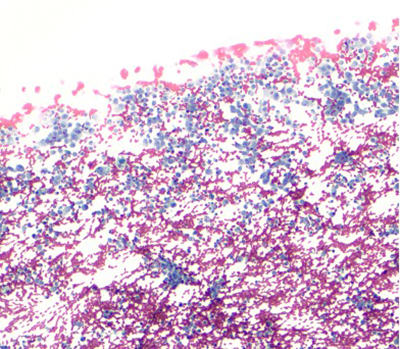

The aspirate was hypercellular and composed of small round cells, distributed in clusters of loosely cohesive clusters and as isolated cells. Moderate pleomorphism, hyperchromasia and variably prominent nucleoli were noted. On cell block preparation, the cytoplasm of these cells had a cleared appearance. Geographic necrosis was noted, with viable cells present in perivascular areas. Focally, there was an extracellular myxoid matrix.

Papanicolaou stain (100X)